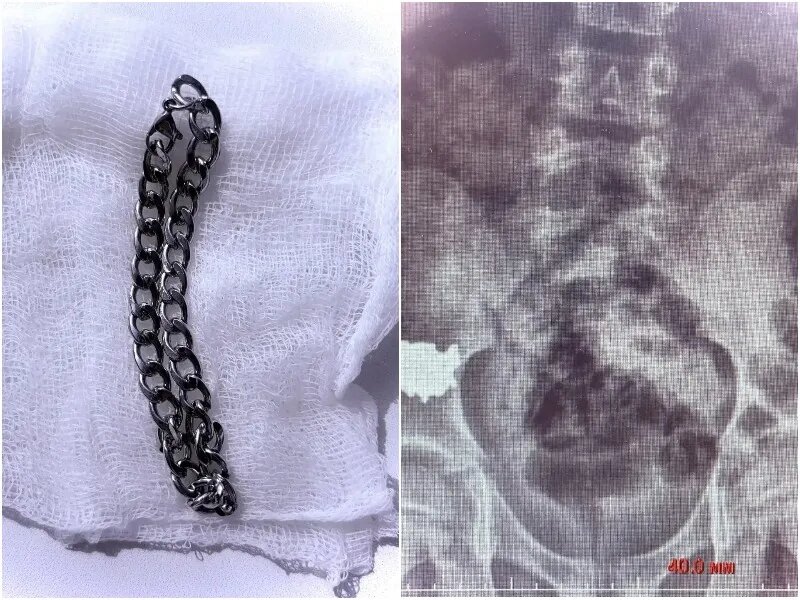

Доигрался: воронежский школьник проглотил 20-сантиметровую цепочку

Врачи успешно прооперировали ребенка, проглотившего длинную металлическую цепочку. Инцидент произошел во время игры: родители заметили произошедшее и срочно привезли школьника в Воронежскую областную детскую клиническую больницу №2.

После поступления ребенку сделали рентген, который показал, что инородный предмет длиной около 20 сантиметров находится в правой подвздошной области — нижней части живота. Пациента госпитализировали для наблюдения и попытались решить проблему без операции, рассчитывая, что предмет сможет самостоятельно продвинуться по желудочно-кишечному тракту.

Однако контрольные обследования, проведенные спустя несколько дней, показали, что цепочка остается на прежнем месте и не продвигается. Как рассказал детский хирург Владимир Кораблев, это создавало серьезную угрозу осложнений, включая повреждение кишечной стенки и развитие перитонита.

В связи с этим врачи приняли решение о срочном хирургическом вмешательстве. Под общим наркозом сначала была выполнена колоноскопия, однако обнаружить инородный предмет таким способом не удалось. Тогда медики провели ревизию брюшной полости.

Во время операции цепочку удалось найти и аккуратно извлечь через просвет аппендикса.